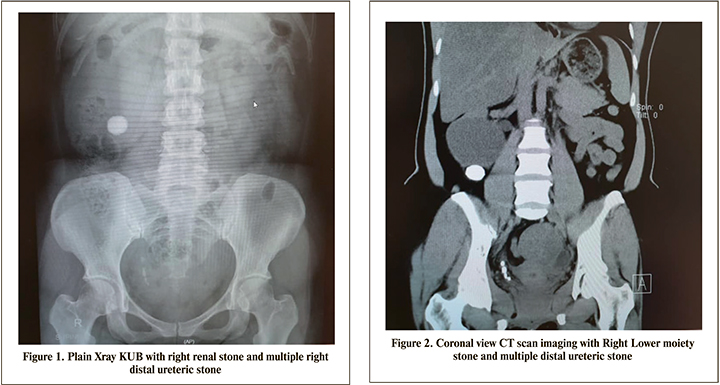

The patient is a 40 years old Malay lady presented with long history of right loin pain associated with radiating loin to groin pain with dysuria. Clinical examination showed no abdominal mass and bilateral kidneys were not ballotable with normal blood investigation results. An Xray KUB was done and showed right renal stone and multiple right distal ureteric stone (Figure 1). An ultrasound KUB performed and showed right hemorrhagic cyst with hydronephrosis. She had a non-contrast CT Kidney, ureter and bladder (KUB) performed and showed a lower moiety stone 1.6 cm x 2.3 cm with multiple distal ureteric stone with hydronephrosis and hydroureter (Figures 2,3 and 4). A CT Renal 4 phase was done and showed a right duplex with bifid ureters and obstructive uropathy due to distal ureteric stone and a right lower moiety renal calculus (Figure 5). She had a Diethylenetriamine pentaacetate (DTPA) scan and showed left kidney with 63.7% and right kidney 36.3% with upper moiety 85.4% and lower moiety 14.6% function. Subsequently a retrograde pyelogram and stenting was attempted but failed due to impacted distal ureteric stones. Hence, she was planned for primary Ureterorenoscopy (URS) and laser lithotripsy and laparascopic transperitoneal right heminephrectomy. Intraoperatively went smoothly and postoperative recovery was uneventful. Complete clearance of stones achieved (Figure 6). Her histopathology report confirmed features of non-functioning kidney with associated chronic inflammation. She was reviewed in the clinic 2 weeks postoperative for removal of stent and a subsequent clinic review with no signs of early and late complications.